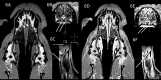

According to current knowledge, the vomeronasal organ (VNO, Jacobson's organ) is the structure responsible for semiochemical signal detection. In dogs and other mammals, it is located close to the vomer and palatine processes of the incisive and maxillary bones. Although there are reports describing the anatomy and histology of this structure, there are limited available reports assessing this organ in live individuals and no direct visualization reports in dogs. The aim of this study was 2-fold: (1) preparation and optimization of a protocol for magnetic resonance imaging (MRI) examination of the VNO in a cadaver study with precise visualization and localization, and (2) characterization of the physiological VNO image features in MRI of live dogs. The first part of the study was performed on 10 beagle cadavers, the second on 8 live beagle dogs. For the VNO visualization, a 1.5T MRI (Philips® Ingenia) scanner and 20-channel digital head-neck spine coil were used (Philips®, Holland). The cadaver study allowed confirmation of the organ's location by the topical application of an MRI contrast agent (gadolinium) via the external entrance of the VNO canal. Accurate delineation of the VNO was obtained using a high resolution submillimeter three-dimensional T1-fast field echo (FFE) 3D sequence. Imaging of the VNO in 8 living dogs allowed the description of the morphological MRI features and direct evaluation of its shape and size. The results obtained demonstrate the ability to visualize the VNOin vivo and to evaluate its structure in dogs.